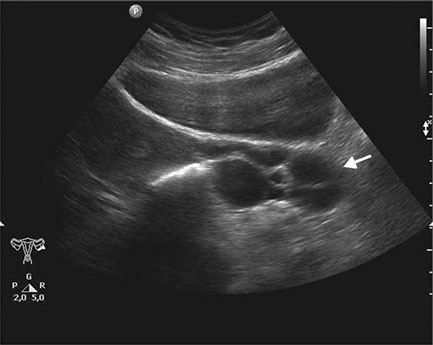

En el caso del ultrasonido pélvico, que te ayudará a la identificación de quistes ováricos o fibromas uterinos y algunas anormalidades endometriales, debes estar preparada acudiendo al centro una hora antes del examen con la vejiga vacía.

En el caso que el especialista te ordene un ultrasonido transvaginal, para obtener una visión más cercana a tus órganos pélvicos, se realizará mediante la colocación de una cámara en la parte inferior del abdomen y mirando a través de la vejiga.